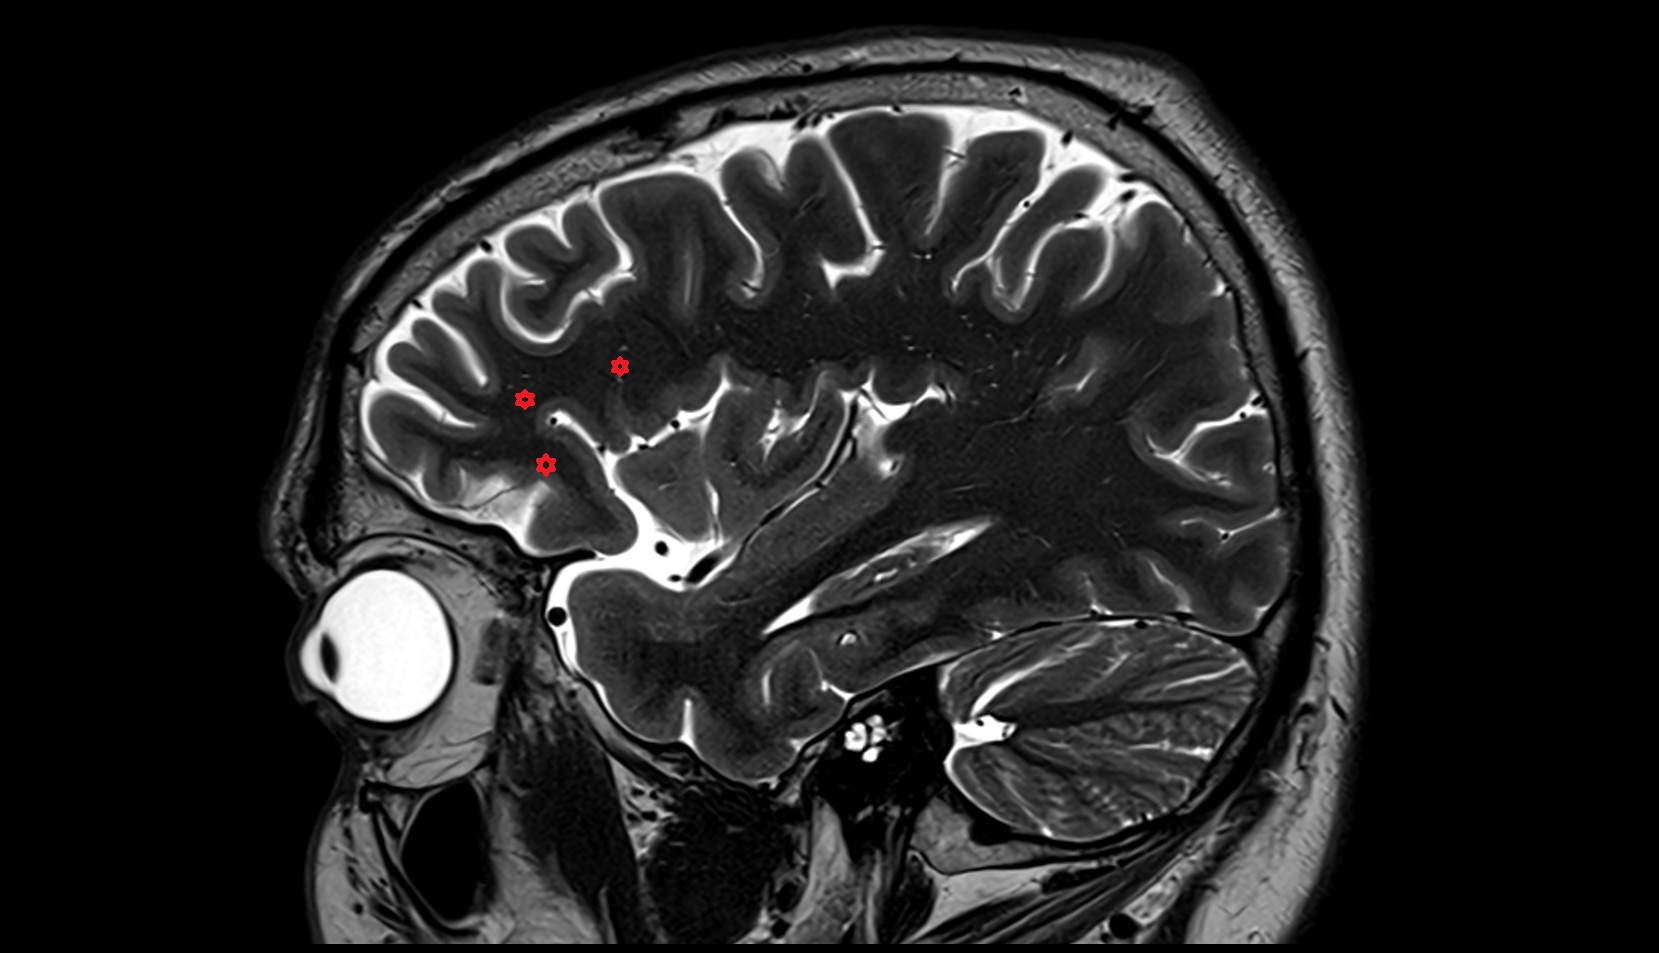

- Central sulcus